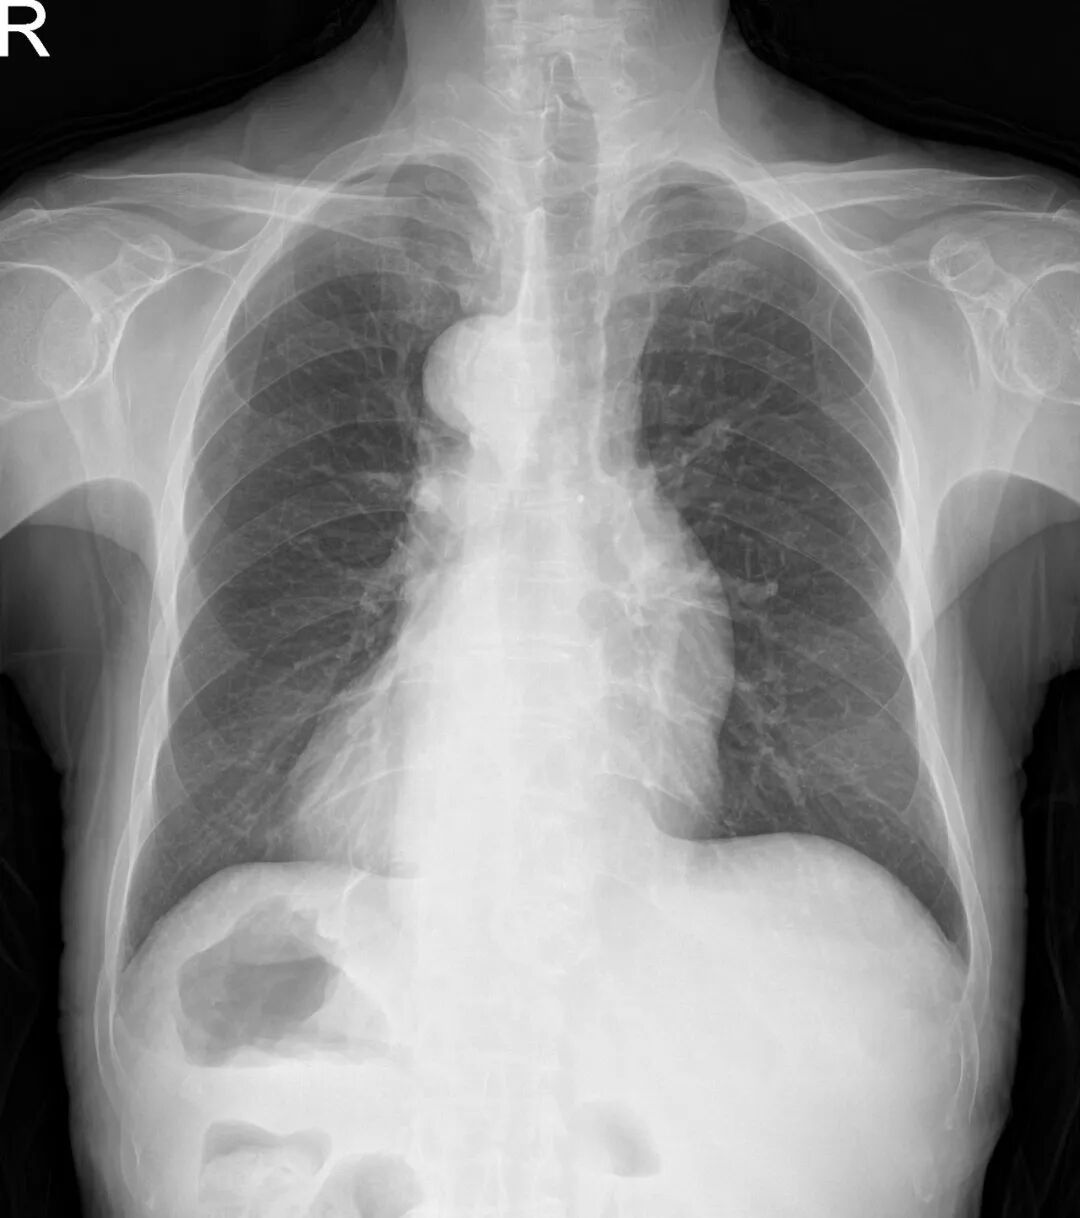

术前影像学提示内脏全反位